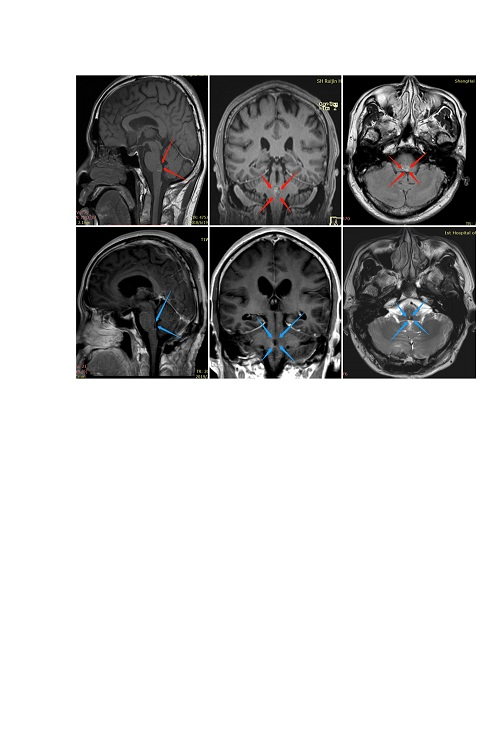

一名有高血压史的62岁女性由于意识突然紊乱而被送往另一家医院。CT扫描显示存在原发脑桥出血。她接受了2周的保守治疗。然而,她的症状没有好转,她被转到德国INI医院。入院时,她表现出意识障碍(GCS评分,13),左侧偏瘫(MMT评分,3),右侧神经III麻痹,左侧面神经(神经VII)麻痹(HB级2)。发病后21天,她通过半枕外侧入路进行手术。患者的意识水平,运动功能,眼球运动和面神经麻痹在术后早期开始好转。术后MRI显示完全切除脑桥血肿。她恢复后神志清,并且独自步行出院。

由于突然意识丧失和构音障碍,一名71岁男子被送往德国INI治疗。入院时,他表现出意识障碍(GCS评分,13),右侧偏瘫(MMT评分,3),左侧神经III和神经VI麻痹,左侧VII麻痹(HB级2)。CT扫描显示存在原发脑桥出血(下图,左起二个)。在发病后6天,在家人提供书面知情同意书后,他通过跨半长位置的半长方位进行手术。血管通过菱形窝从面部三角区撤离.尽管他的眼球运动仍然受损,但他的意识水平,运动功能和面部麻痹在术后早期开始好转。术后MRI显示完全切除脑桥血肿。